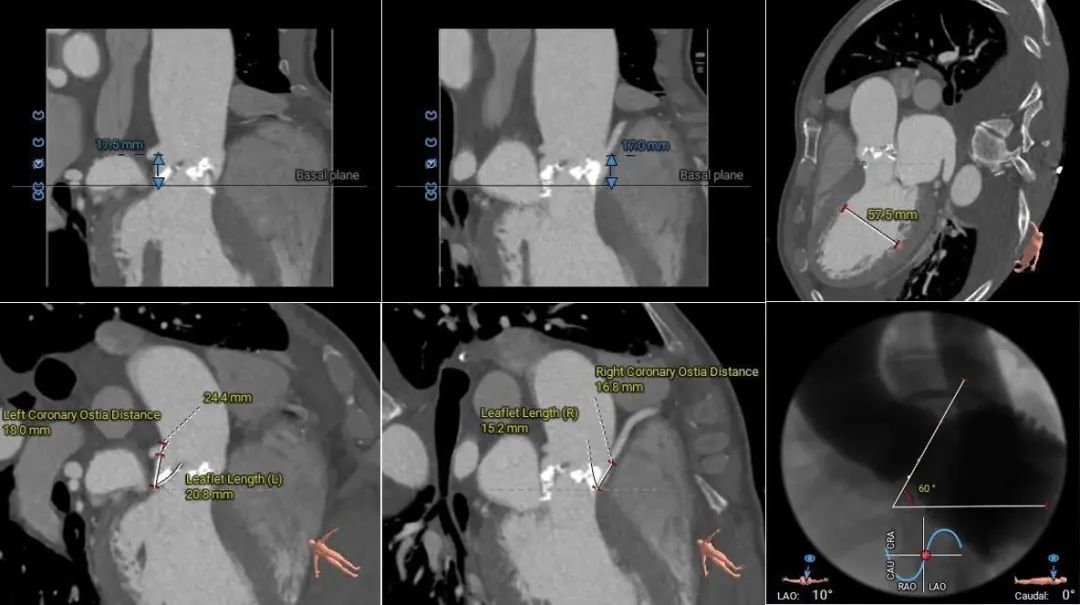

术前CT评估

Type-1型二叶式主动脉瓣,瓣叶重度钙化并增厚,钙化主要分布在瓣叶及管壁附着缘上;

左右冠开口高度可,双侧冠脉切线位瓣叶长度<冠脉开口上缘到瓣叶附着缘距离,无明显钙化分布;

左室心腔内径增大,LVOT呈敞口状,瓦氏窦内径和升主动脉内径增宽,窦管交界内径可;

主动脉瓣环水平夹角60°,横位心,主动脉弓角度及弓距可;

主动脉根部测量

瓣上结构测量

冠脉阻挡风险、左室大小及横位心评估